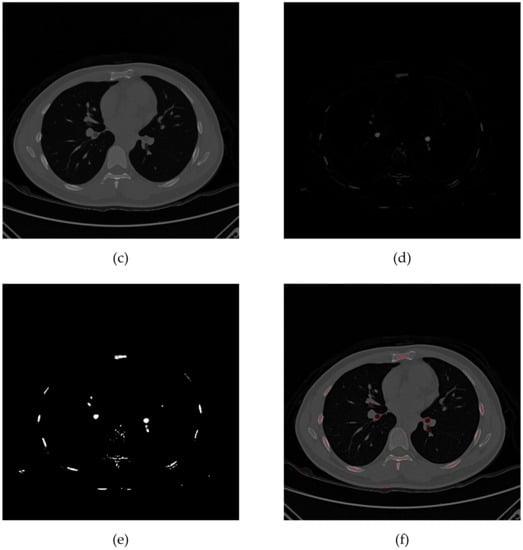

After filling, the closed dark pixels are detected by the grayscale reconstruction method, as shown in Figure 6. Grayscale reconstruction masks of different detection radii are connected using a six-adjacency relation to complete pulmonary airway detection. Figure 7 shows the 3D visualization result of the circled airways.

Figure 6.

Grayscale reconstruction flow chart. (a) Original image; (b) labeled image; (c) grayscale reconstruction image; (d) local difference image; (e) local valley target; (f) original image marked with local valley target.